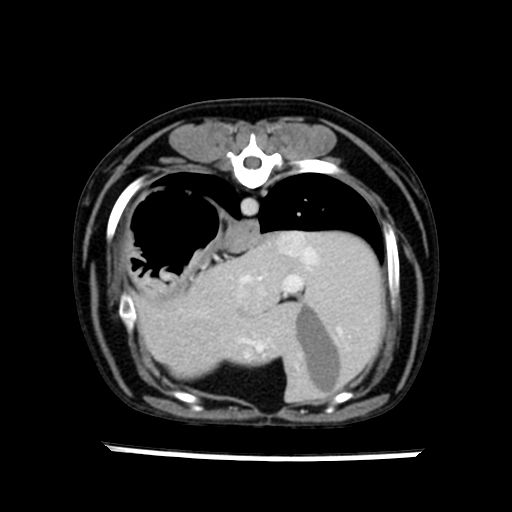

prescritto esame TAC

sequenza immagini limitata al fegato reni e surreni

sospetto adenoma ipofisario vs. meno probabilmente meningioma della base; intertiziopatia polmonare; lesione espansiva epatica, verosimilmente del lobo laterale sinistro, di sospetta natura neoplastica; lesioni spleniche di natura da definire; iperplasia/ipertrofia delle ghiandole surrenali, bilateralmente; vertebra di transizione del rachide toracico; tenosinovite cronica del muscolo bicipite brachiale di destra.

- Nessuna informazione diversa per quello che riguarda l’esame ecografico del fegato e la presa del contrasto si confermano le lesioni individuate e l’ipoenanchement in fase portale.